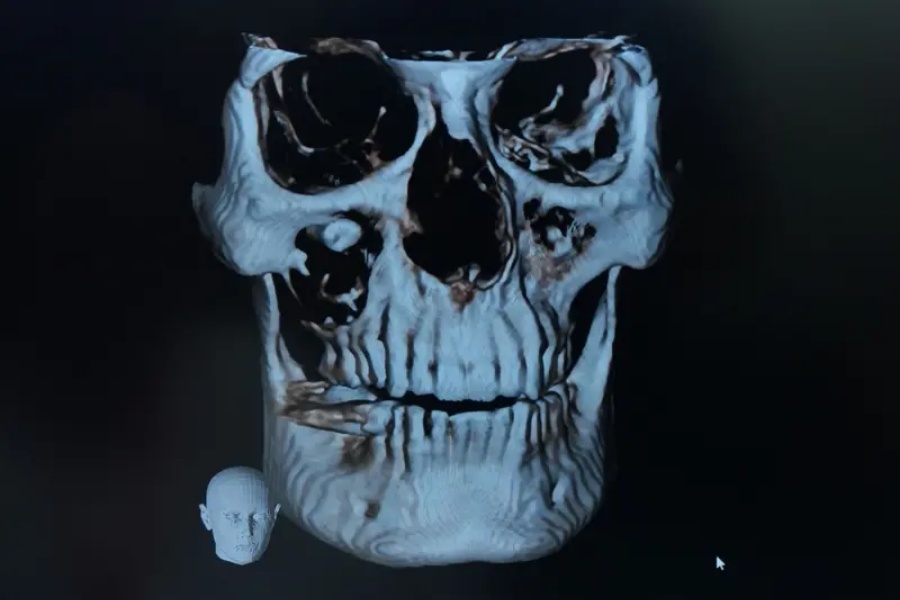

पटना आएर उनले आईजीआईएमएसमा दन्त चिकित्सकसँग परामर्श गरें। डाक्टरले मेरो सीबीसीटी स्क्यान गराएर हेर्दा उनको आँखामा दाँत भएको देखियो। शल्यक्रियापछि आफू अहिले पूर्ण रूपमा स्वस्थ भएको उनले बताए।

सीबीसीटी भनेको कोन बीम कम्प्युटेड टोमोग्राफी हो। सरल शब्दमा भन्नुपर्दा, यो एक प्रकारको एक्स-रे हो। यसले म्याक्सिलोफेसियल (बंगारा र अनुहार) क्षेत्रको एक्स-रे गरेर थ्रीडी तस्वीरहरू बनाउँछ। दन्त विभागको म्याक्सिलोफेसियल, ओएमआर (ओरल मेडिसिन र रेडियोलोजी) र एनेस्थेसिया शाखाहरूले संयुक्त रूपमा उपचार गरेका थिए।

रमेश कुमारको दाँतको जरा त्यही 'फ्लोर अफ द अर्बिट'मा पुगेको पाइयो। यसबारे प्रियंकर विस्तृतमा बताउँछन्, "यस अवस्थामा, दाँतको जरा फ्लोर अर्बिटमा थियो। जबकि यसको क्राउन भाग (दाँतको सेतो भाग) म्याक्सिलरी साइनसमा थियो। यो दाँत यसको सामान्य ठाउँमा नबनाइएको हुनाले, यो शरीरको लागि 'विदेशी शरीर' जस्तै थियो।"